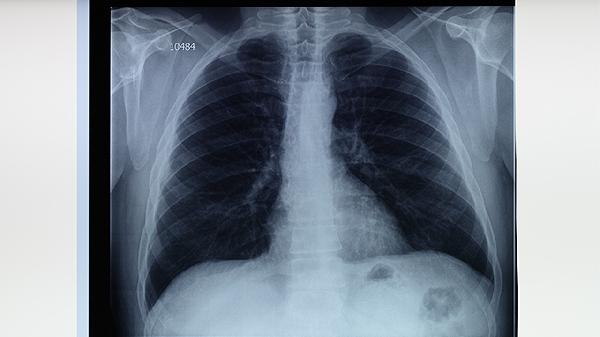

对共同居住者、同事等密切接触者进行结核菌素试验和胸部X线筛查。15岁以下儿童及免疫缺陷者需预防性服用异烟肼片3-6个月。发现疑似病例立即转诊至定点医院,建立接触者健康档案跟踪监测2年。